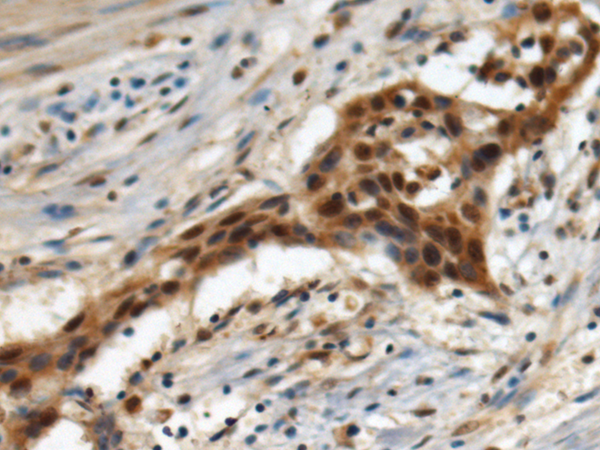

EIF3G |

eukaryotic translation initiation factor 3 subunit G |

IHC positive control: |

Human esophagus cancer |

IHC Recommend dilution: |

100-300 |